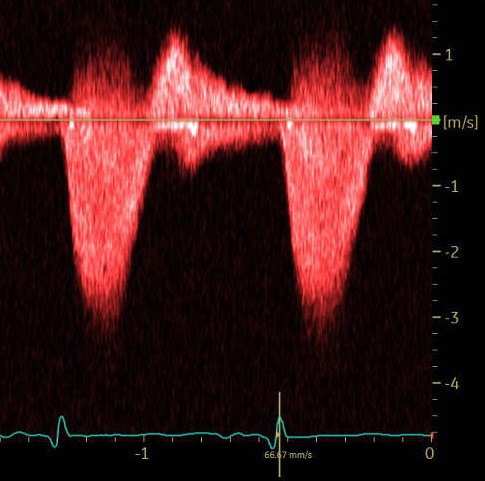

2-sinus of Valsalva bicuspid AOV! 4D TTE vs 4D TEE! Donal Alex Felix Özge Özden Kayhan Luigi LEYLA ELIF SADE Nicolas Merke Vladyslav Kavalerchyk 🇺🇦